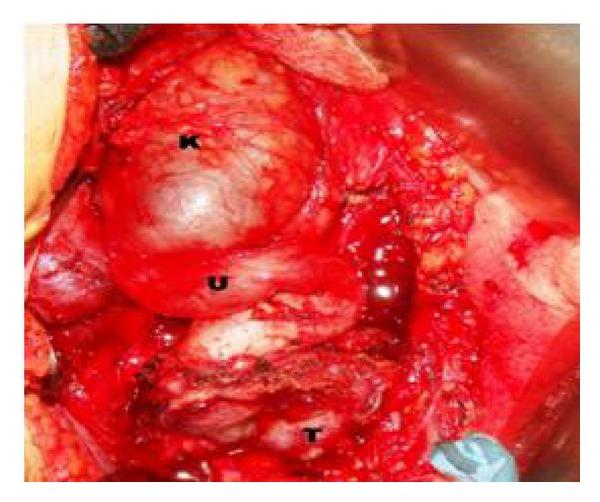

Paragangliomas are neuroendocrine tumors that arise from sympathetic nerve ganglia. They can develop anywhere from the neck to the pelvis, but are most commonly found in the abdomen, particularly at the aortic bifurcation or in the periaortic region. Malignant paragangliomas account for 29-40% of cases. We report a case of 36-year hypertensive female presented with and right flank pain and accelerated hypertension. On evaluation she was diagnosed to have non unctioning kidney due to malignant pelvic paraganglioma with right ureteric encasement. We believe our case is one of the first reported in literature as rare presentation of malignant paraganglioma presenting as nonfunctioning kidney and accelerated hypertension.

副神经节瘤是起源于交感神经节的神经内分泌肿瘤。它们可发生于从颈部到骨盆的任何部位,但最常见于腹部,尤其是在主动脉分叉处或主动脉周围区域。恶性副神经节瘤占病例的29% - 40%。我们报告一例36岁高血压女性患者,表现为右侧胁腹疼痛和高血压急症。经评估,她被诊断为因恶性盆腔副神经节瘤侵犯右侧输尿管而导致右肾无功能。我们认为我们的病例是文献中首次报道的以无功能肾和高血压急症为罕见表现的恶性副神经节瘤之一。